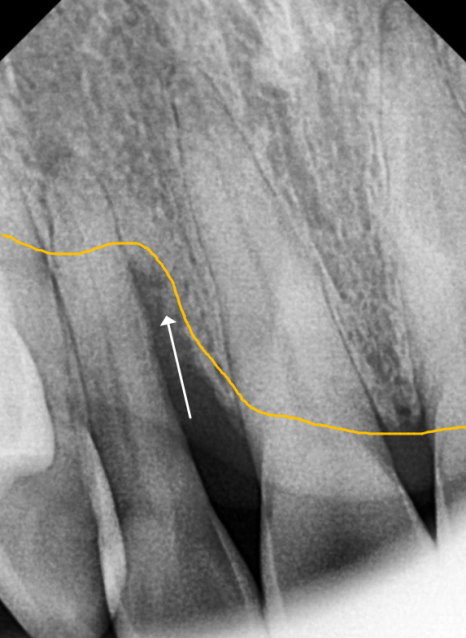

방사선 사진을 살펴볼게요~

매끈해보여야 할 치아 뿌리 쪽에

돌기처럼 무언가 붙어있는게 보이시나요?

251201

바로 치석인데요.

사실 치석은 밀도가 낮아

방사선 사진상에는

잘 나타나지 않는 경우가 많아요.

그런데 만약 엑스레이 사진에서

이처럼 치아 옆면이 매끄럽지 않고

돌기처럼 튀어나온 것이 보인다면,

정상적인 잇몸 상태 , 치아 뿌리 면이 매끄러움

치은연하치석이 뿌리면에 돌기처럼 붙어있는 모습

그건 치석이 이미 엄청나게

두껍고 단단하게 쌓였다는 뜻이에요..ㅜㅜ